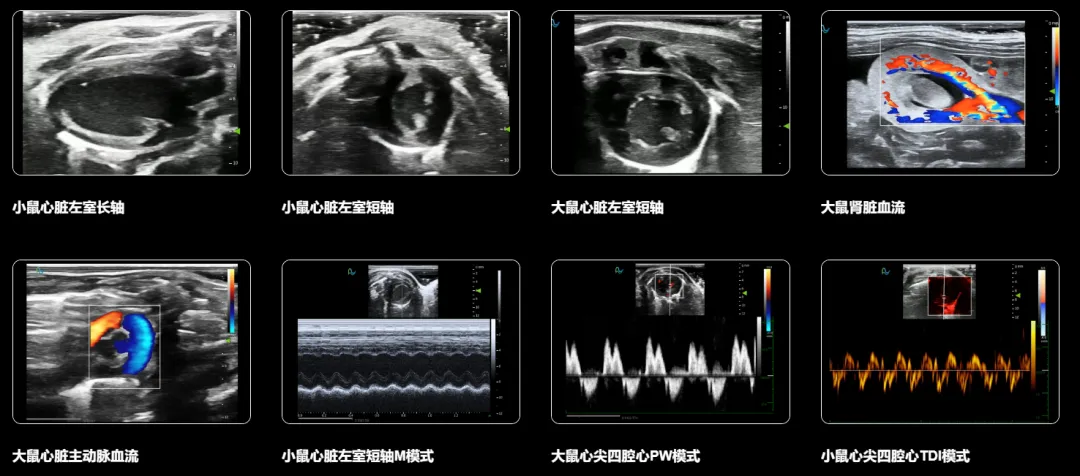

从B超、M超到彩色多普勒、脉冲多普勒,再到心肌应变成像,3D/4D成像和脑功能成像,Sonorover集成了多种先进的成像模式,为科研人员提供全方位、多角度的观察视角。特别是高帧频造影成像、3D/4D成像、超分辨率超声成像等功能,更是将科研探索推向了新的高度。

先进成像效果